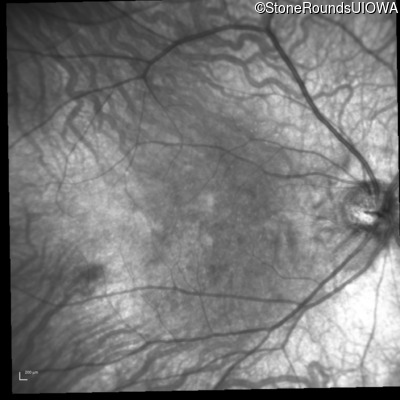

Infrared Fundus Photograph - Right - 20/80 +2

Exemplar